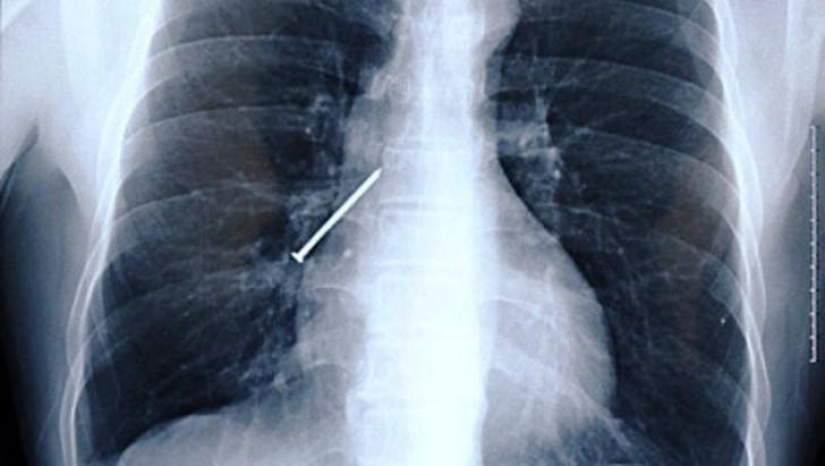

Clavo.